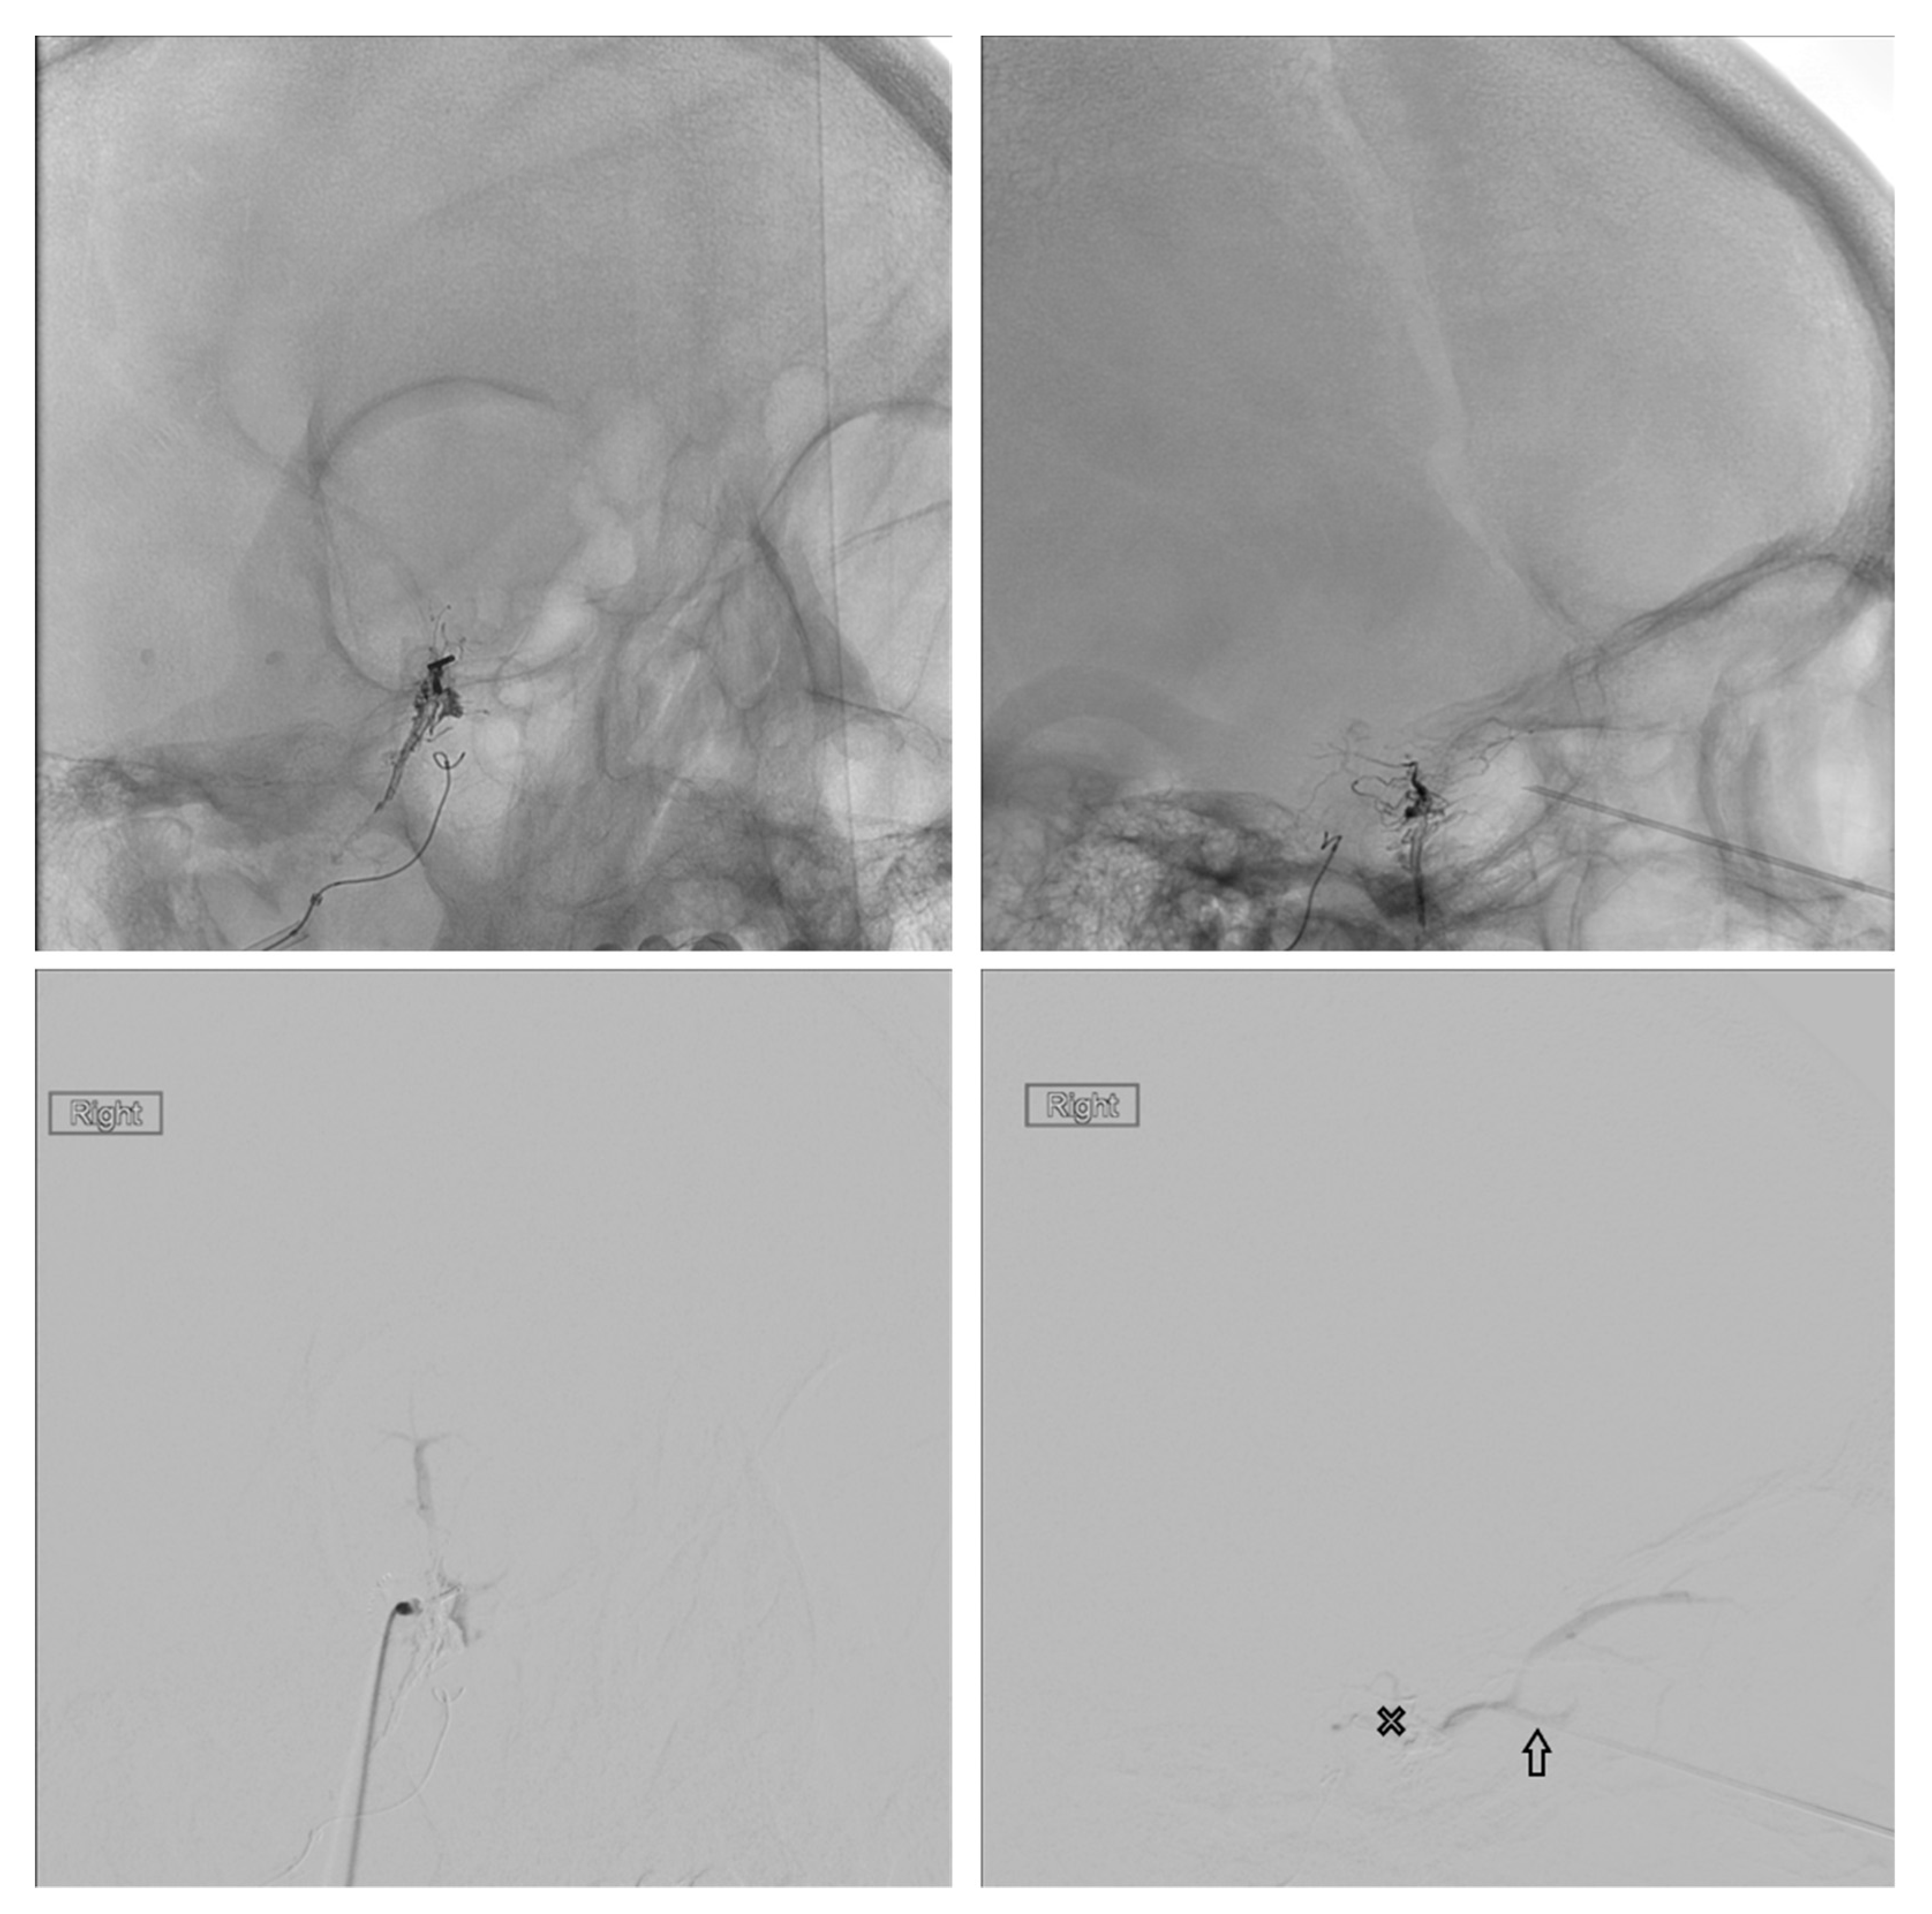

Figure 8. Demonstrates access to the cavernous sinus (X) via surgical exposure and cannulation of the SOV (arrows).

Figure 9. Demonstrates surgical exposure of the lateral wall of the right cavernous sinus via a pre-temporal approach (left). The arrow shows the site of spinal needle puncture in the lateral wall of the cavernous sinus.